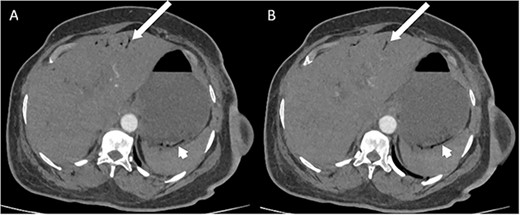

Whilst awaiting her planned orthopaedic surgery, the patient developed epigastric and retrosternal chest pain on Day 13 of admission, associated with persistent vomiting and abdominal distension. On examination, she had a moderately distended abdomen, with no focal peritonism present. Initial blood tests performed showed mildly elevated inflammatory markers, normal serum troponin levels, and a raised D-dimer. As such, a computed tomography (CT) pulmonary angiogram was initially performed; whilst no evidence of pulmonary embolism was identified, an incidental finding of gas within the liver peripheries (Fig. 1A) and the gastric fundal wall was noted (Fig. 1B). A subsequent plain film abdominal radiograph performed showed a significantly distended stomach (Fig. 2).

Plain film radiograph of the abdomen demonstrating a distended and gas-filled stomach.